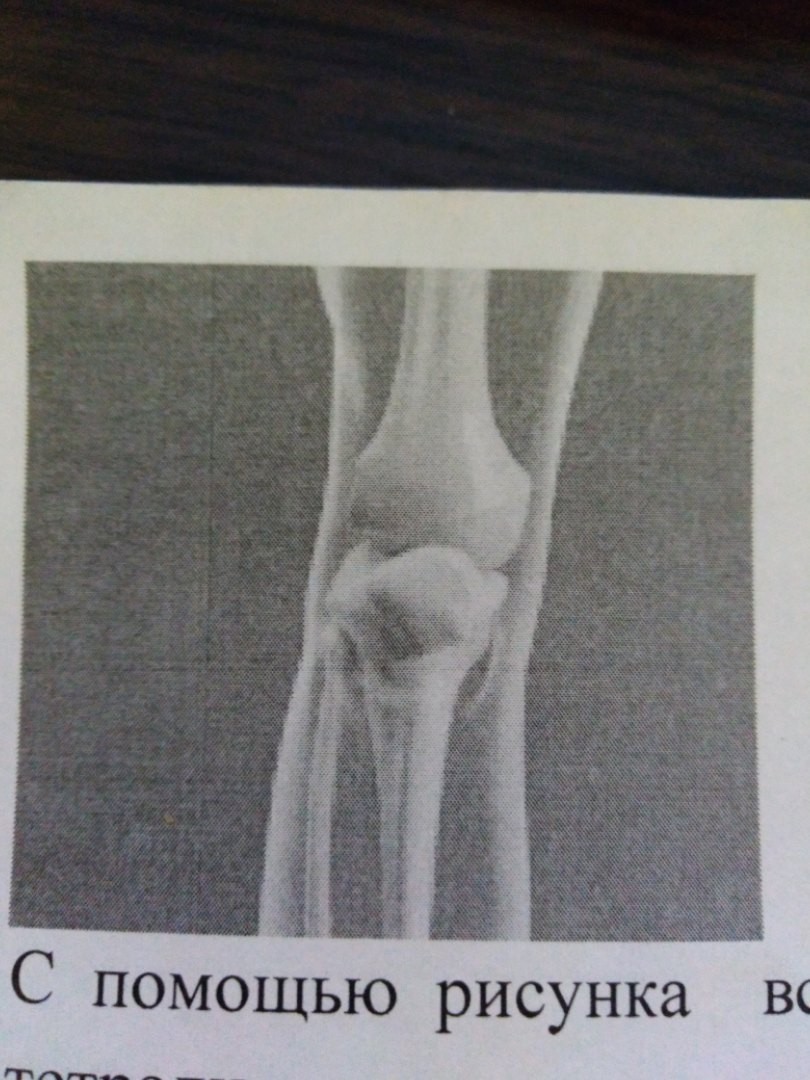

• С помощью рисунка вспомните части, составляющие сустав. Перечислите их в тетради.